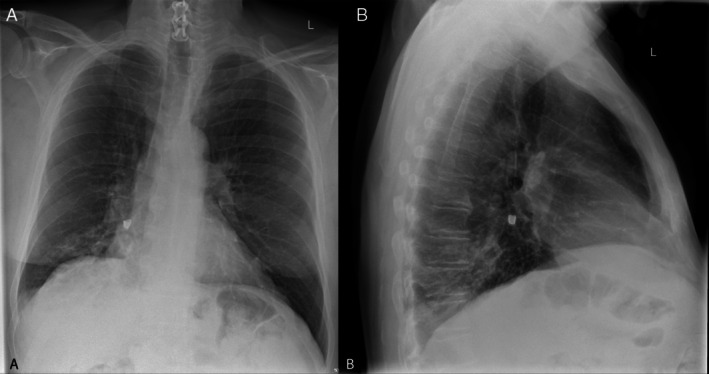

A Crumpet, a Canine and a Cryoprobe: A Case of Tooth Aspiration.

Foreign body inhalation can lead to post-obstructive pneumonia and sepsis, requiring timely removal to achieve source control. We report a case of tooth aspiration successfully retrieved with a cryoprobe.